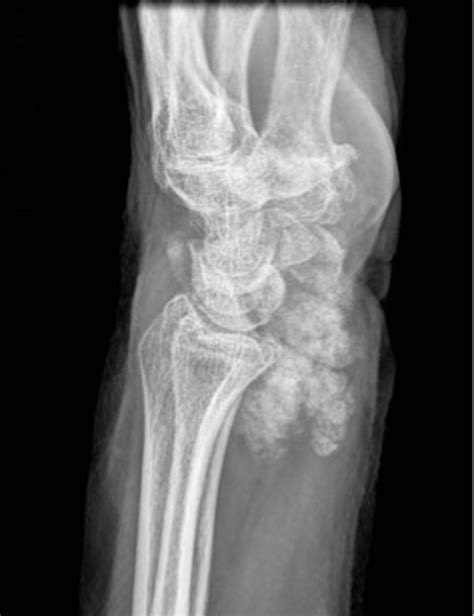

New Medical Reports Detail How Calcified Feet Develop Over Time